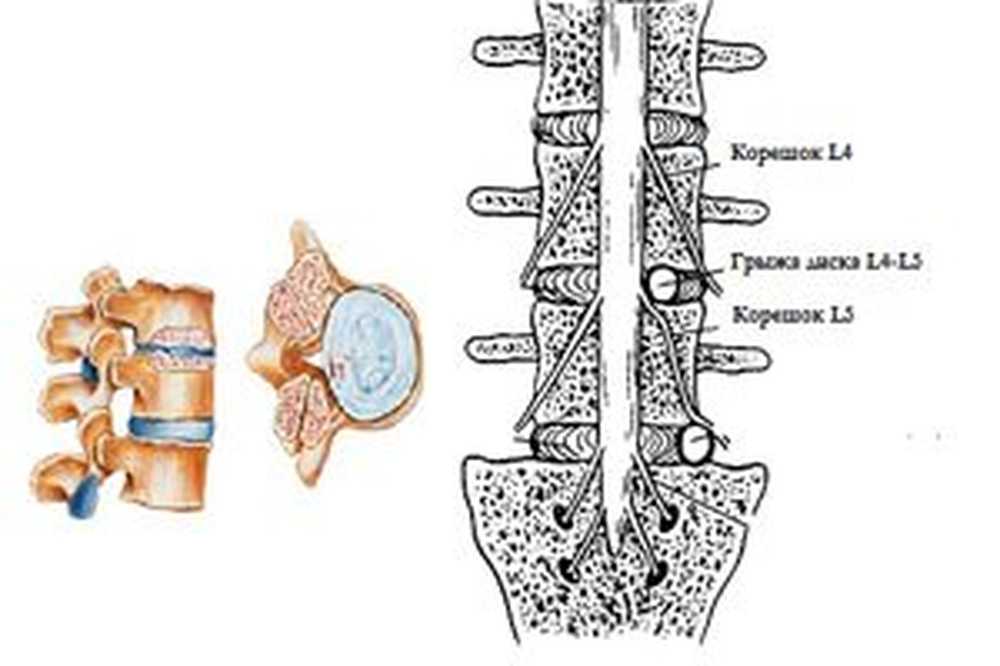

КТ-протрузии дисков: Визуализация и классификация